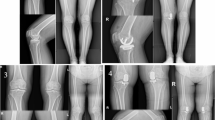

A total of 900 studies were identified in this study. After review of the titles, abstracts, full articles, and excluding unrelated articles 17 studies involving 2612 knees were eligible and selected for the final meta-analysis1,5,8,9,10,11,12,13,14,15,16,17,18,19,20,21,22 (Fig. 1). Three of the 17 eligible studies were randomized controlled trials (RCTs). Weight or body mass index (BMI) was reported in 11 studies. The mean follow-up period ranged from 7-months to 17.2-years; the follow-up period was not stated in two studies. Additional details about study characteristics and participant demographics are shown in Table 1.

Within the 17 eligible studies the FB knee prostheses were from seven manufacturers: Miller-Galante (Zimmer), Robert Brigham (Johnson and Johnson), St Georg Sled (Waldemar Link), Preservation All Poly (DePuy), Optetrak (Exactech), Allegreto (Centerpulse), and Accuris (Smith and Nephew); the MB knee prostheses were from two manufacturers: Oxford (Biomet) and AMC (Alphanorm).